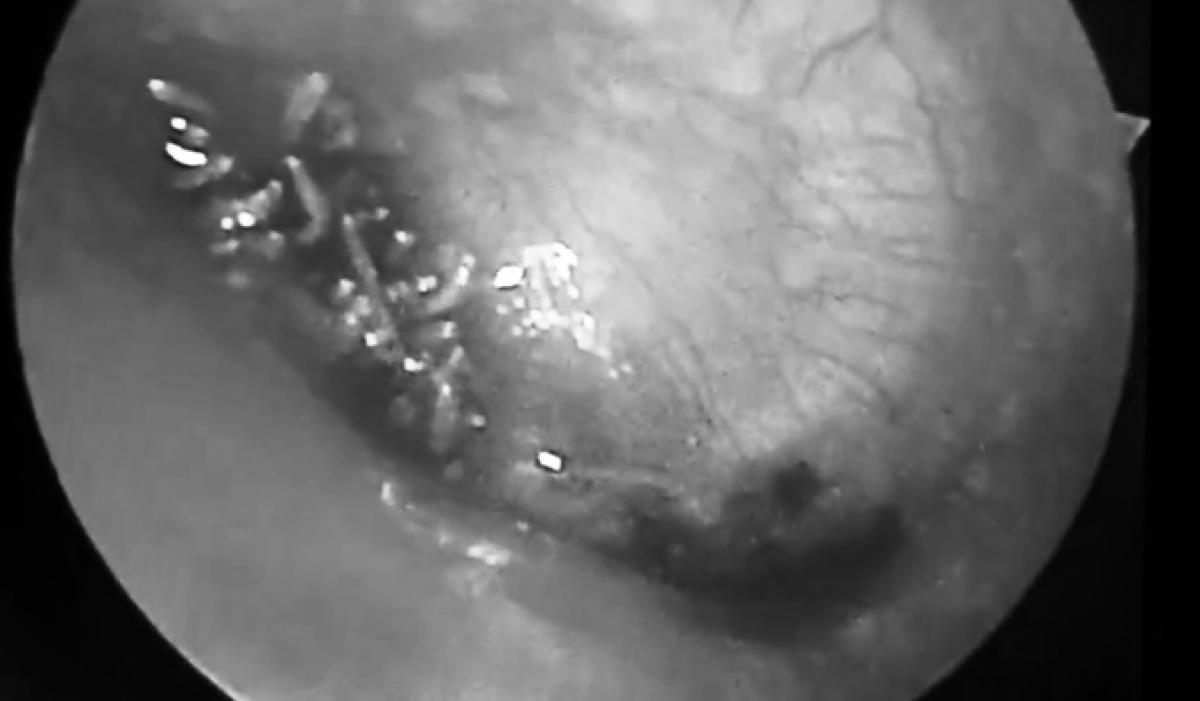

Người bệnh cho biết bị con nhặng xanh bay vào tai và đã được lấy ra. Mấy ngày sau, ông đau tai, chảy dịch nên đến Bệnh viện đa khoa An Phát khám. Nghi có dị vật, bác sĩ nội soi tai mũi họng, phát hiện hàng chục con giòi tại khung nhĩ trước màng nhĩ tai phải.

Các bác sĩ vệ sinh, gắp ra khoảng 40 con, kích thước rất bé. Tuy nhiên, số lượng giòi quá nhiều, nằm sát màng nhĩ nên không thể gắp hết. Bệnh nhân được chuyển xuống bệnh viện đa khoa tỉnh để tiếp tục xử trí.

Theo chuyên gia, mọi người thường mắc các dị vật khác nhau trong tai, mũi như hạt đỗ, hạt muồng, hạt của các loại đồ chơi, mảnh bông gòn, cục phấn, cục tẩy, pin cúc hay các loại côn trùng như kiến, muỗi... Trường hợp giòi làm tổ trong tai với số lượng lớn như bệnh nhân này rất hiếm, lần đầu bệnh viện tiếp nhận. Bác sĩ mất 1,5 tiếng để gắp, thêm ba tiếng xử trí tại cơ sở tuyến tỉnh mới sạch được toàn bộ, "số lượng giòi có thể lên đến cả trăm con".